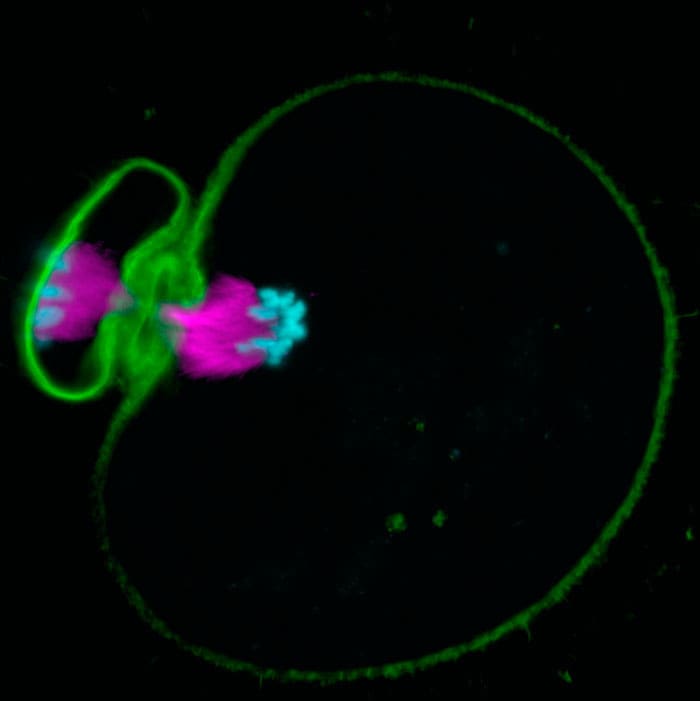

Finding the genes that are responsible for controlling accurate progression through meiosis is hugely important for understanding why human eggs so often contain errors. RNA interference (RNAi) is a method for systematically blocking the production of specific proteins, so that scientists can find out the role of each one. However, oocytes contain lots of stored proteins, so this interference would need to be started from a very early developmental stage to completely block each protein. Sybille Pfender, Vitaliy Kuznetsov and Michał Pasternak in Melina’s group developed a screen where they microinjected short interfering RNAs (siRNAs) into very small follicle-enclosed mouse oocytes and grew the follicles in vitro, blocking the protein expression while they grew. They waited until the oocytes had reached their full size before imaging them live with confocal microscopes to study the function of targeted genes.

This is the first RNAi screen for meiotic genes in mammals and its development has allowed Melina’s group to analyse the function of nearly 800 genes, identifying many new genes involved in mammalian meiosis. The screening also created huge amounts of data showing how mammalian chromosomal defects arise. Many couples find it difficult to conceive and rely on in vitro fertilisation to achieve their dreams of having a family. This screening technology will help to develop methods that could improve fertility treatments in the long term.